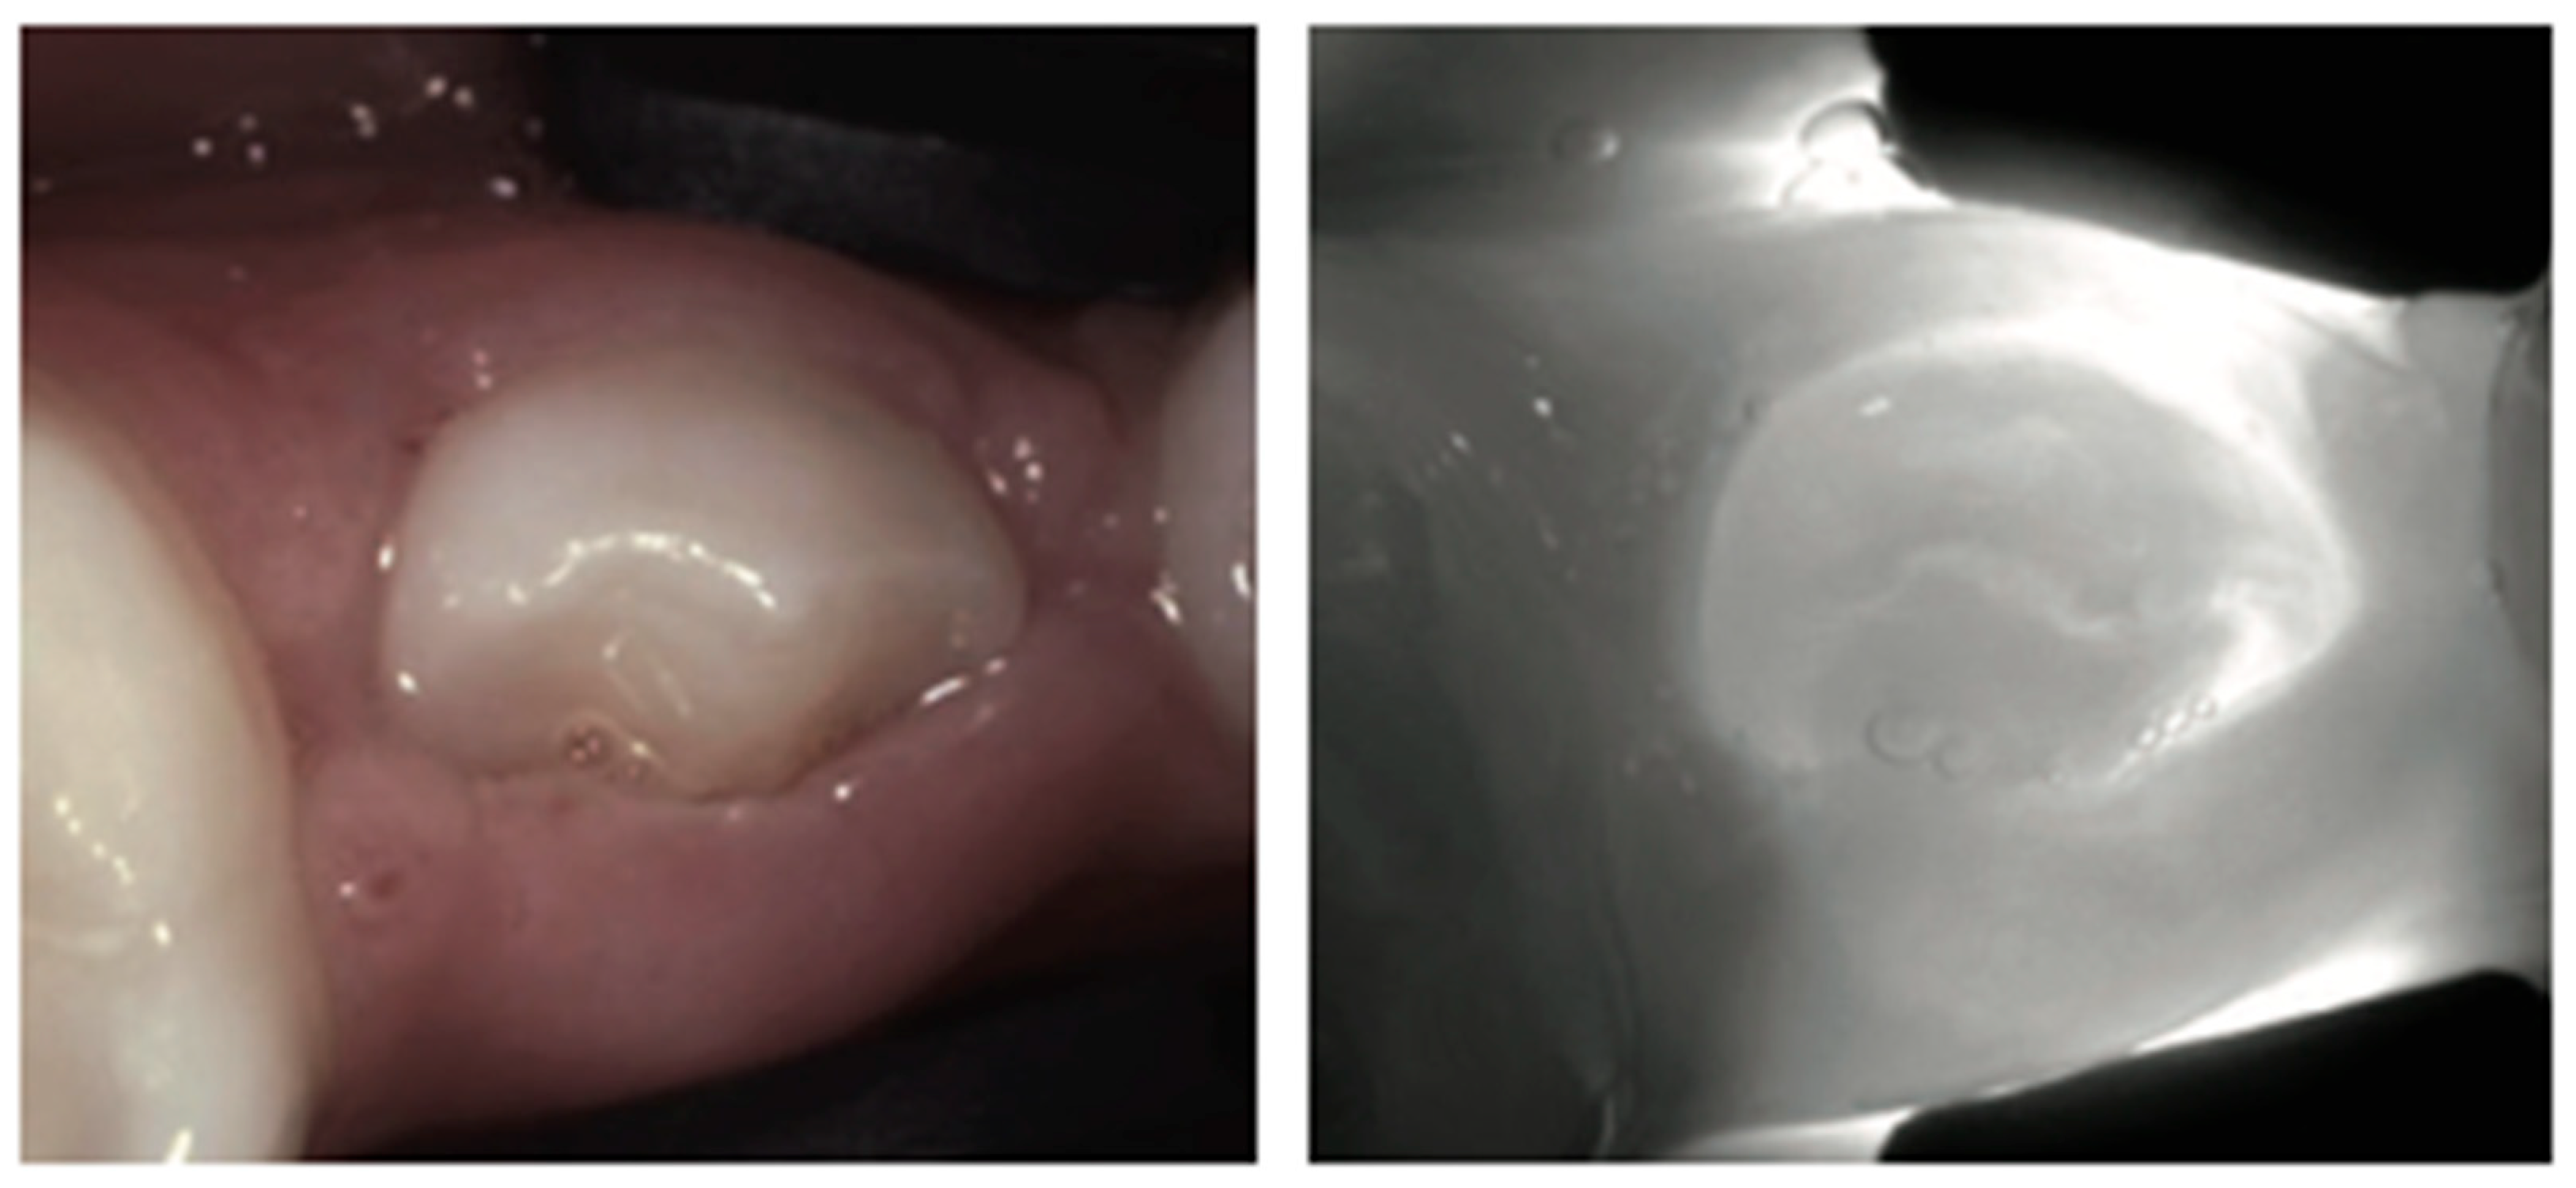

1. Healthy Teeth